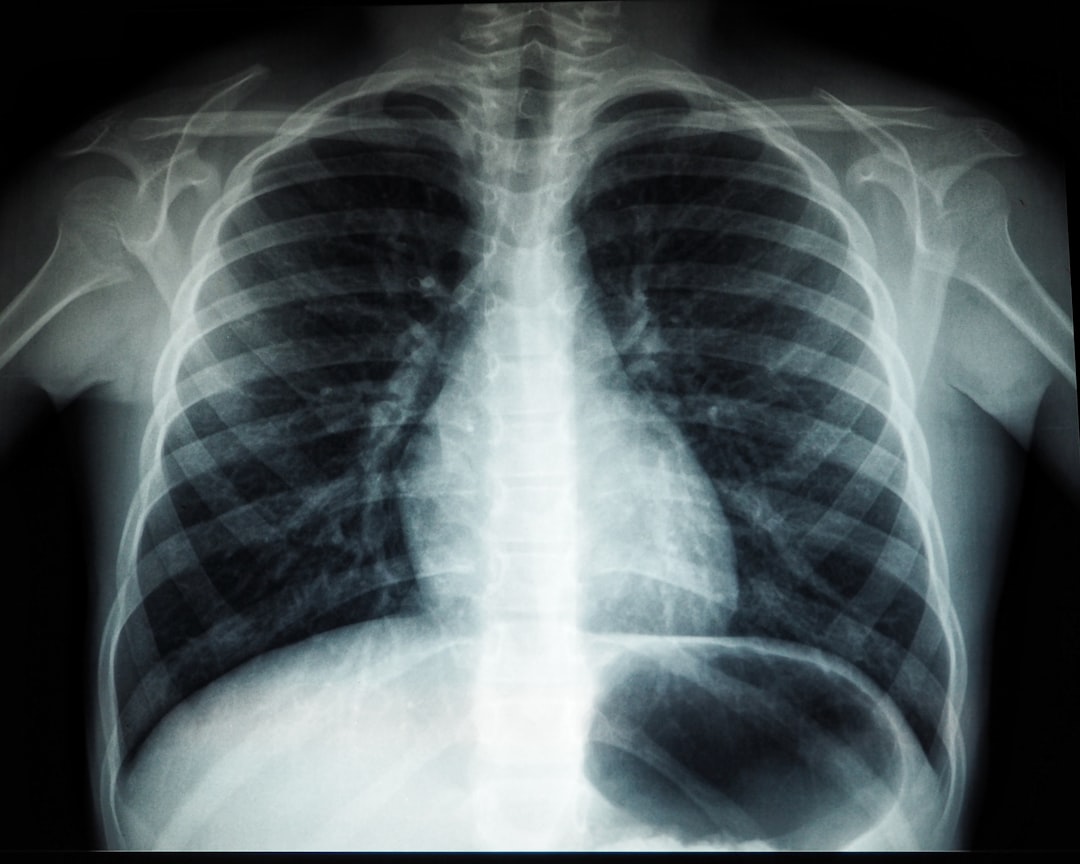

잠복결핵 검사 비용은지역에 따라 조금씩 달라질 수 있습니다. 일반적으로 보건소에서 진행하는 경우는 비교적 저렴한 편입니다. 잠복결핵 검사 비용는 약 20,000원에서 30,000원 사이가 일반적이며, 일부 병원에서는 의료 실비가 적용될 수 있어 더 저렴해질 수 있습니다. 하지만, 검사에서 의사가 필드 진료를 권장할 경우 추가 비용이 발생할 수도 있습니다.

검사에 따른 비용이 걱정되신다면, 보험을 통해 처리가 가능함을 알려드립니다. 많은 보험사에서 잠복결핵 검사 비용에 대한 보장을 제공하고 있습니다. 따라서 검사 전, 보험 가입 여부 확인이 필요합니다. 검사비용은 물론 정기검사나 치료에 필요한 비용이 체계적으로 지원되어야 개인의 건강을 안정적으로 다룰 수 있습니다.